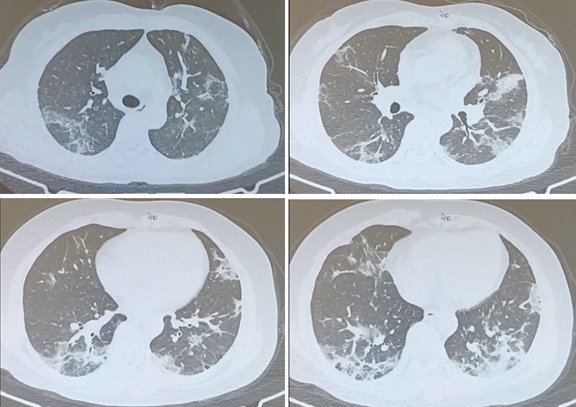

>影像学比较有特征性,肺部CT显示双肺弥漫性毛玻璃影

case1:一位48岁男性,有高血压病史10年,肥胖(BMI 31kg/㎡),这是发病第10天的胸部CT,显示双肺弥漫性浸润影和磨玻璃影。患者的呼吸困难进行性加重,鼻导管吸氧5L/min,指测氧饱和度只有93%,稍一活动即呼吸困难,接种过3剂的疫苗。

case2:一位49岁女性,有类风湿关节炎14年,卵巢癌术后10年,长期服用泼尼松、雷公藤、甲氨蝶呤。这是发病第13天肺部CT显示双肺弥漫性斑片影和磨玻璃影。呼吸困难进行性加重,咳嗽咳黄痰,呼吸频率24-25次/分,鼻导管吸氧2L/min,SpO2 96%。

case3:87岁男性,糖尿病、冠心病,2022年12月11日,双肺弥漫性的毛玻璃影,如果照一张胸片,大家就会看到白肺。(河北邢台总医院张翠云大夫、中日医院PCCM科王一民大夫提供)

case4:这个病例来自北京朝阳医院发热门诊,谷丽主任提供。男,50岁,无明显基础疾病。我们可以看到他双肺弥漫性的毛玻璃影,也是典型的病毒性肺炎。